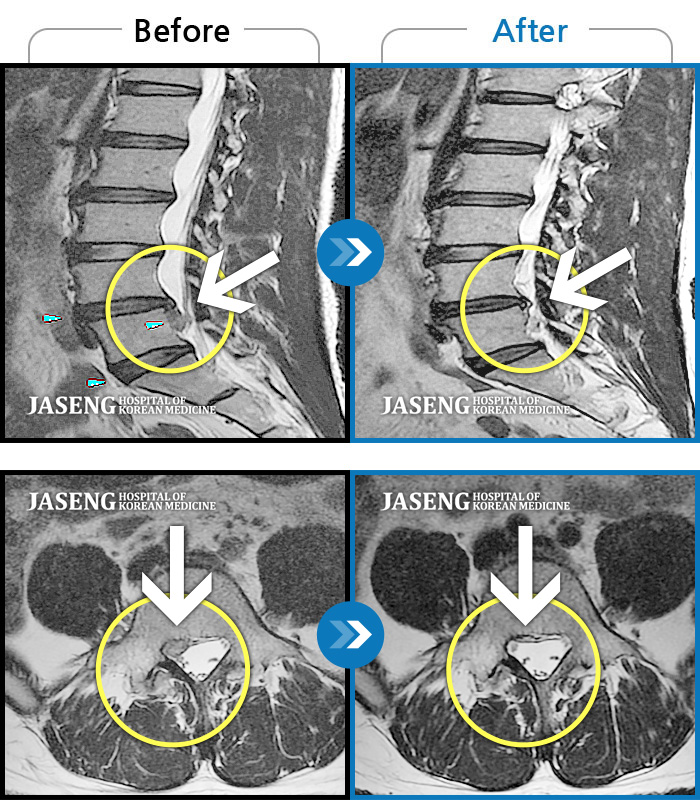

허리디스크

보라매 · 빈상은 원장

좌측 허리부터 고관절 통증이 심하고 다리까지 저려서 허리를 똑바로 펴기 힘들어요.

촬영시기

2020.07.27 ~ 2023.01.20

2023.11.24

조회수 514